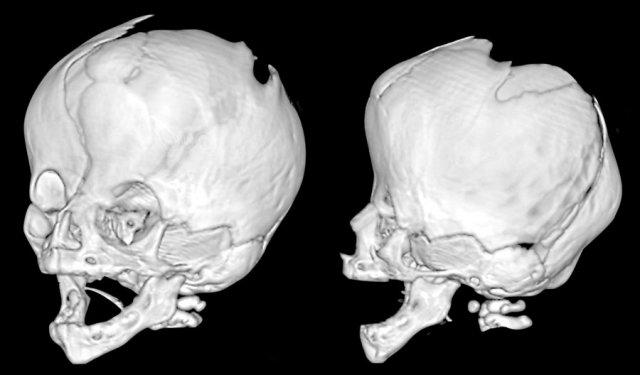

Hội chứng Saethre-Chotzen. Ở trẻ hai tháng tuổi, có hình ảnh dính khớp vành hai bên với hình dạng hộp sọ biến dạng nặng nề. Thóp được mở rộng đáng kể.

Cùng bệnh nhân như trên.

Ở ba tuổi, có hình ảnh đầu nhỏ do tình trạng gần như dính toàn bộ khớp sọ.

Lưu ý hình ảnh lỗ đỉnh hai bên giãn rộng.

Trẻ ba tháng tuổi mắc hội chứng Pfeiffer.

Có hình ảnh dính khớp vành hai bên với thóp trước và thóp chũm giãn rộng.

Sự phồng ra ở vùng thái dương tạo nên hình ảnh ba thùy, còn được gọi là ‘dị dạng đầu lá cỏ ba lá’.

Lưu ý hình ảnh giãn não thất kèm phù quanh não thất.